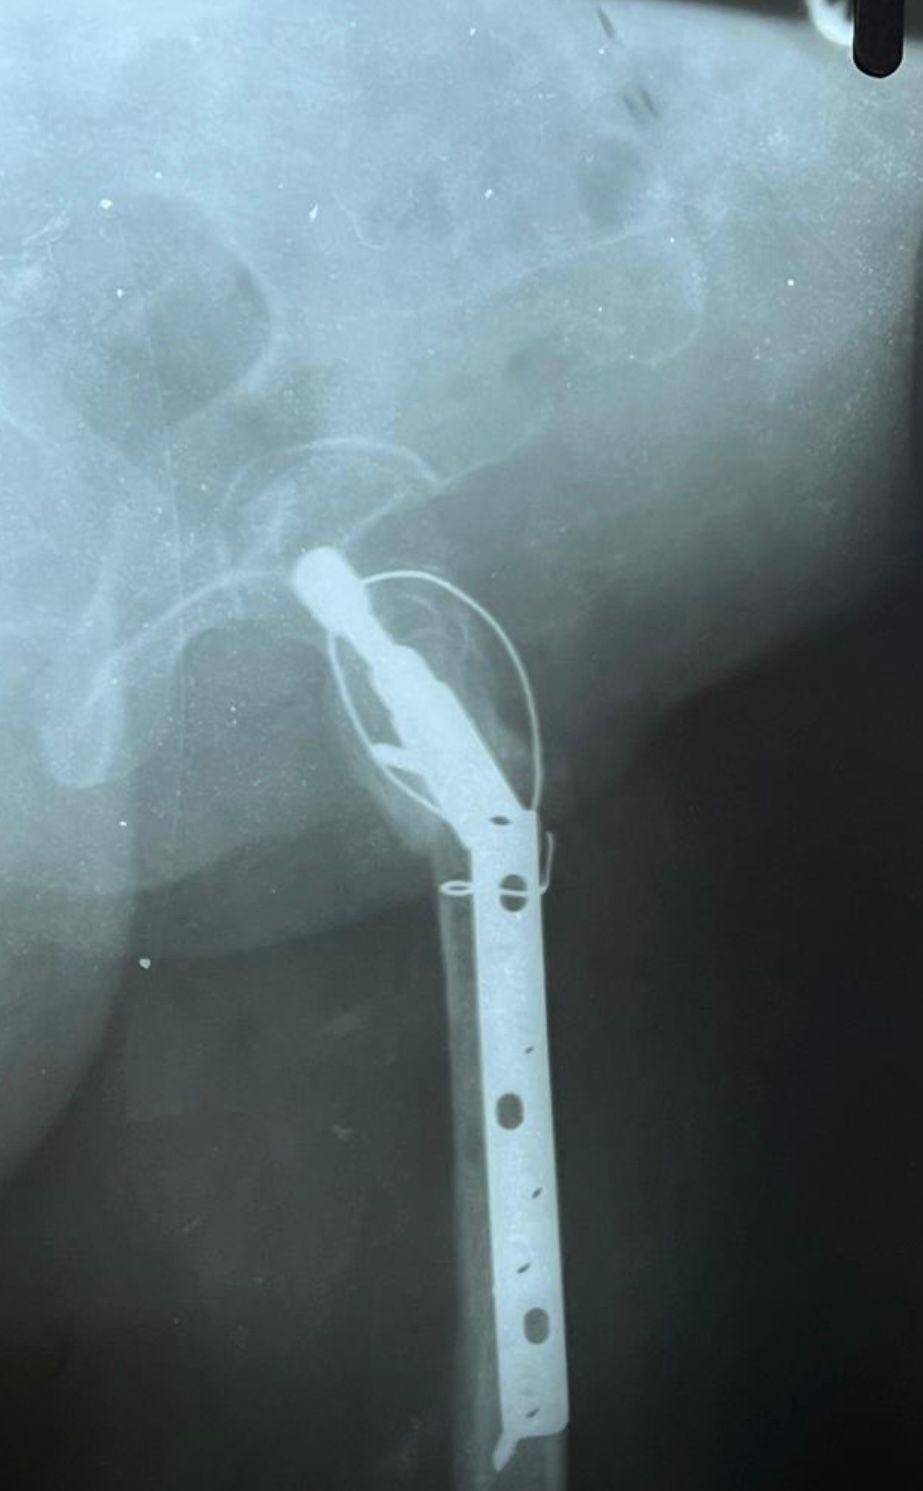

Non union with Broken DCS implant & revision

correction surgery